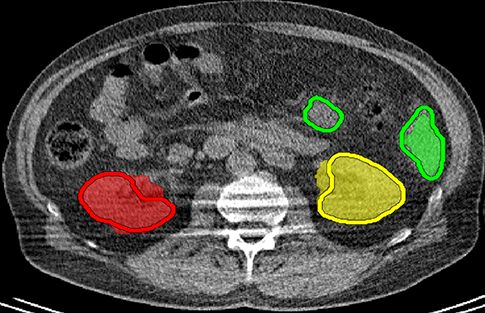

We applied our method on PET-CT scans of three different subjects to segment their liver, left kidney, right kidney and the background. Although we applied our method and Potts model on the 3D volumes we only show the results on a few representative slices from each volume in Fig.11. Also, the results of different methods for each subject were computed using the same smoothness. We can see from the last two rows which compare our method to Potts, using Hedgehogs constraints enabled us to avoid geometrically incorrect segmentations, e.g. one liver inside the other (last-row middle), or parts of left kidney is between the right kidney and liver (last-row right). Furthermore, for test subjects 1 and 2 the kidneys and background were poorly segmented by Potts model, e.g. most of the kidneys were segmented as background for test subject 1. Potts poor performance is due to the large overlap between the kidneys and background color models. This overlap resulted in an in-discriminative data term for Potts to properly separate them. This issue becomes worse in iterative frameworks where color models are re-estimated based on current segmentation. To be specific, if at any iteration Potts model resulted in a bad segmentation then re-estimating the color models will bias them towards the bad segmentation and subsequent iterations worsen the results. Comparing our results for subjects 1 and 2 to Potts model shows that our method is less prone to the aforementioned issue as we forbid undesirable segmentations, i.e. those that do not respect shape constraints.

| Subject 1 | Subject 2 | Subject 3 | |||

| Our method (Hedgehogs Shapes + Potts) | ![]() |

| \rdelim}1910pt Same Slice | |||||

|

Potts |

For quantitative comparison, Table 1 lists for each organ of a subject the Score, Precession and Recall measures of our method and Potts model where For the kidneys, our method clearly out performed Potts model, e.g. note Potts model poor precision/recall for subjects 1 and 2. For the liver, both methods performed comparably.